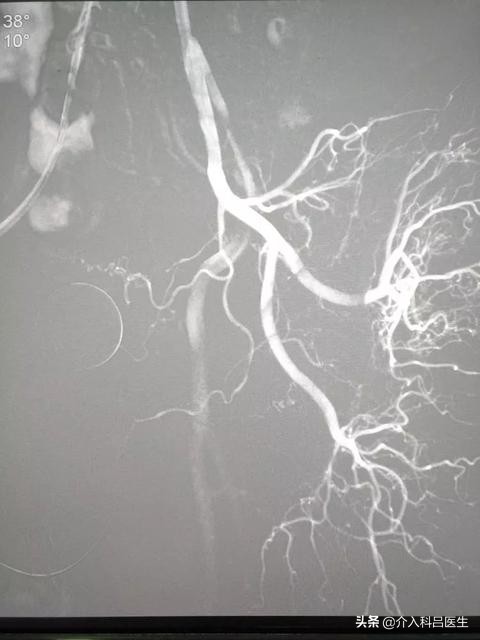

检查完后,我们就为王大爷安排了手术,由于患者年龄大、血管迂曲,前列腺动脉介入栓塞难度大,其主要体现在前列腺的供血血管非常纤细,周围组织比较多。

为了减少对周围组织的损害,使用微导管超选到前列腺动脉内进行栓塞。前列腺动脉的交通支比较丰富,前列腺动脉完全栓塞以后,前列腺还有直肠下动脉、会阴动脉和膀胱上动脉供血,因而不会产生坏死。微导管超选进入前列腺动脉,避开了周围组织,因而不会产生性功能障碍。